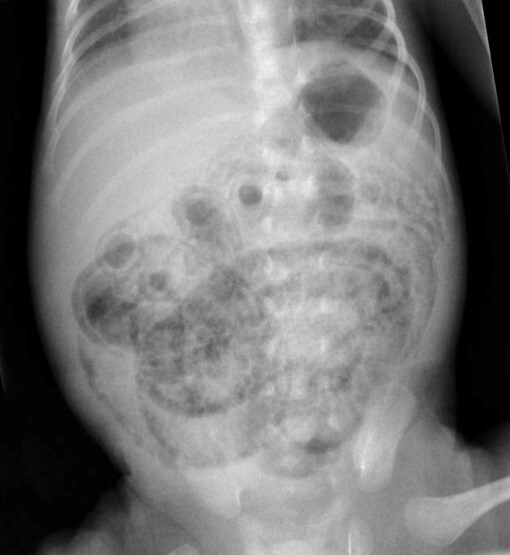

necrotizing enterocolitis (gas shadows because air in GI submucosa) it looks like rings

(gas shadows because air in GI submucosa) it looks like rings

necrotizing enterocolitis

: Hemorrhagic necrosis beginning in the mucosa, and extends to involve the muscular wall. Intestinal villi are seen disintegrating, loss of nuclei and has reddish cytoplasm. The mucosal wall in the right slide shows pneuomatosis

Necrotizing Enterocolitis (NEC)

After being born, 2 weeks later the baby is brought back with symptoms of bloody stool and abdominal distention. Gas tracks are seen along the bowel wall, cystic “bubbly” collections. Air is collected in intestinal wall, but if it is intraluminal air accumulation 🡪 Hirshsprung’s

Necrotizing Enterocolitis (NEC) There is hyperreactivity to bacteria which produces Toll-Like Receptors. Mass is seen in duodenal area